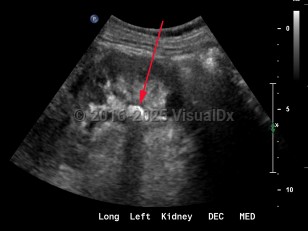

Renal calculus

As many as 80% of the stone disease in the United States are calcium oxalate or calcium phosphate stones. Calcium stones form when the concentration of these solutes (calcium, oxalate, or phosphate) exceed the solubility threshold of the urine in which they are dissolved. The solubility of these solutes is influenced by urine pH, the presence of other free ions, urinary organic solutes, and the presence of other crystals which provide nucleation sites for new crystal formation. When the urine is supersaturated and other factors are favorable, crystals form and precipitate, forming either stones inside of the renal pelvis or in submucosal plaques eponymously known as Randall plaques.

Although asymptomatic stones are frequently discovered with radiographic imaging, the most common presentation is sudden-onset flank pain radiating to the groin, accompanied by nausea and vomiting. This colicky pain (renal colic) typically waxes over the course of 15-30 minutes and becomes steady, unrelenting, and unbearable. Patients may experience worsening paroxysms of pain lasting 20-60 minutes as the stone courses downward through the ureter and as the ureter spasms. If the stone's descent is arrested at the ureterovesical junction, patients may experience urinary frequency, dysuria, and urgency and are predisposed to the development of urinary tract infections both from the stone forming as a nidus for bacterial growth and from the mechanical urothelial trauma caused by the stone's movement. Most individuals with nephrolithiasis will also develop hematuria, particularly when passing a stone.